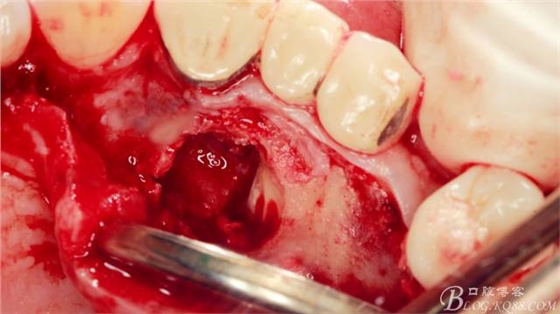

術(shù)中

局麻下做齦溝內(nèi)切口

翻瓣,長柄球鉆清掃薄薄的骨皮質(zhì),暴露出牙冠,動作一定要輕柔,感覺就像在雞毛撣子一樣撣花瓶上的灰一樣,因為骨和牙釉質(zhì)有明顯的密度差異,手感上面差別比較明顯。

長柄裂鉆分離牙冠,微創(chuàng)挺插入后順時針或者逆時針輕擰一下,手上去感受牙冠斷開的那一瞬間,有時候耳朵也能聽見啪得一聲,不過此刻因為牙冠周圍的骨阻力,牙冠是不能取出的。

T形分牙,把牙冠分為兩瓣,減少阻力。

分別挺出兩瓣牙冠,可見牙根截斷面。

微創(chuàng)挺直接挺出牙根。

取出牙根,清理創(chuàng)面。